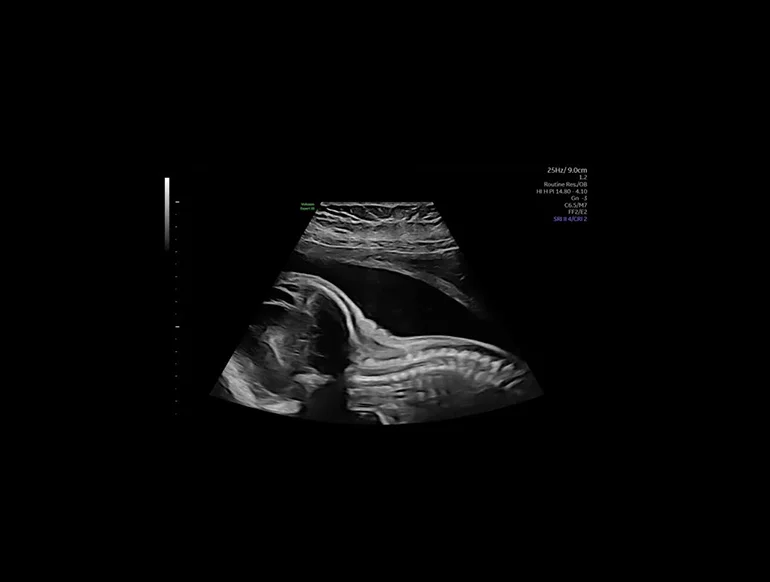

Дуга аорты плода (26 недель), технология Radiantflow

Проводите высококачественную 2D- и 3D-визуализацию, а также цветовую допплерографию с повышенной степенью проникновения и невероятной четкостью, получая изображения важных деталей для обеспечения точности диагностики. Lyric Architecture открывает перед вами новые возможности визуализации и обработки, обеспечивая инструменты развития на годы вперед

Откройте для себя уникальные возможности визуализации, позволяющие с легкостью обнаруживать тонкие анатомические структуры в 2D-, 3D- и 4D-режиме.